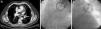

In the chest computed tomography (CT) study, a “cuff-like” soft tissue lesion with peribronchovascular distribution was identified in the left upper lobe, which was initially interpreted as a possible tumour (Fig. 1A, arrow). Although there was clinical suspicion of pulmonary vein stenosis as the cause of the haemoptysis, due to the radiological finding, it was decided to perform bronchoscopy with a flexible endoscope to take a biopsy in order to exclude a tumour at that level; the bronchoscopy revealed a mucosa with petechiae which bled easily as the bronchoscope passed. During the procedure, the patient experienced major bleeding from the left main bronchus, which required selective orotracheal intubation of the right main bronchus and transfer to the intensive care unit.

A pulmonary angiography was performed, showing stenosis of the left upper pulmonary vein (Fig. 1B, in which a decrease in the vascular calibre can be observed at the level of this vein). Balloon angioplasty was then performed at this level, achieving repermeabilisation, with subsequent good angiographic results (Fig. 1C). After the patient had been stabilised and then discharged, he was admitted on a scheduled basis 2 months later for angioplasty with stent placement.

Haemoptysis has been described in the literature as a rare form of presentation of pulmonary vein stenosis,2 but the aetiopathogenesis of the haemoptysis in these patients has not yet been clarified. Aguilar-Cabello et al.3described a similar case in which histopathological examination of a lobectomy sample showed congested lung tissue. The increase in venous pressure in the pre-stenotic zone would explain the lung tissue congestion and the risk of bleeding at the level of the mucosa in this area. In our patient, the image observed initially on the chest CT scan (Fig. 1A) appears to correspond to oedema and peribronchovascular fibrosis secondary to congestion due to thrombosis of the vein. This radiological finding may help to understand the pathophysiology a little more, and serve as a reference to help other clinicians to support the diagnosis of this entity.